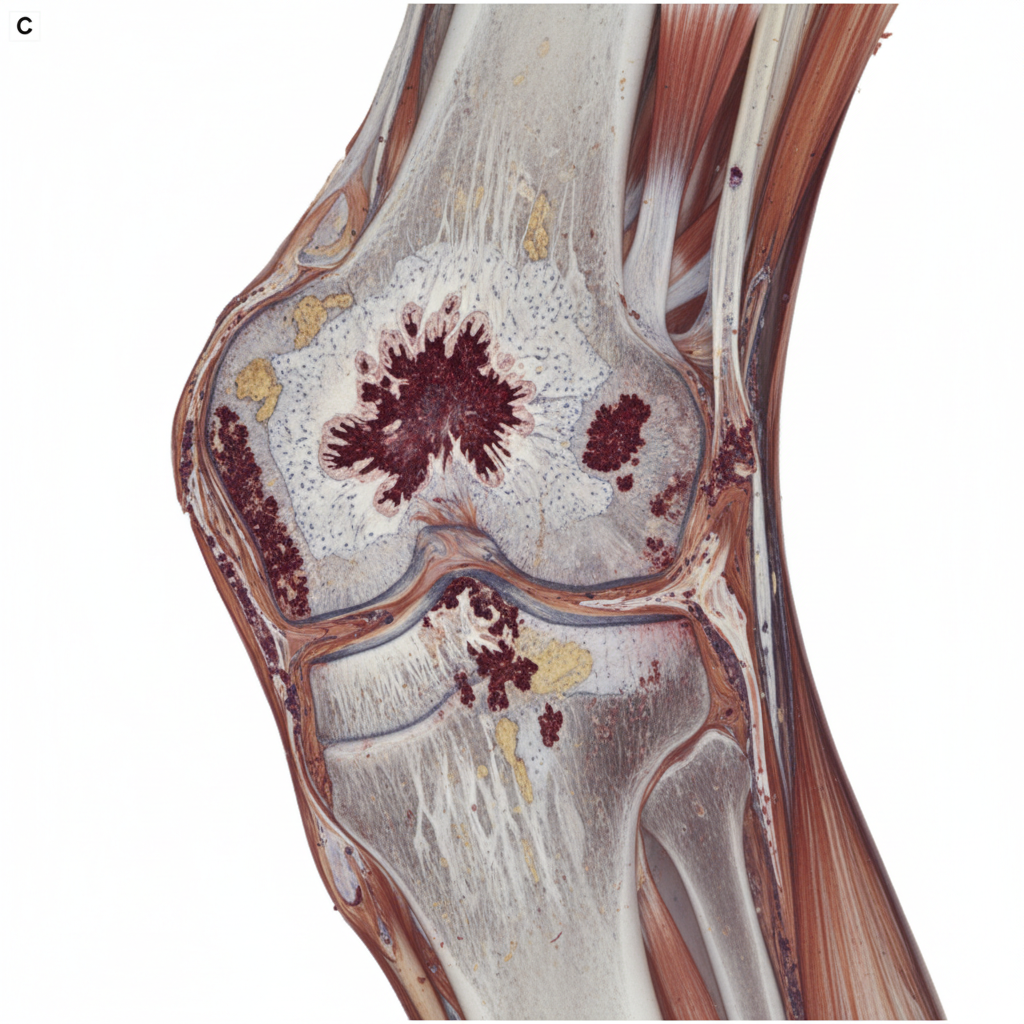

A 68-year-old man comes to the physician because of a 5-month history of undulating, dull pain in his right thigh. Physical examination shows a tender, round mass located above the right knee on the anterior aspect of the thigh. An x-ray of the right thigh shows sunburst pattern of osteolytic bone lesions in combination with sclerotic bone formation and invasion of the surrounding tissue. Despite limb-sparing attempts, the patient has to undergo amputation of the right leg. A photograph of a cross-section of the affected leg is shown. Which of the following is the strongest predisposing factor for this patient's condition?